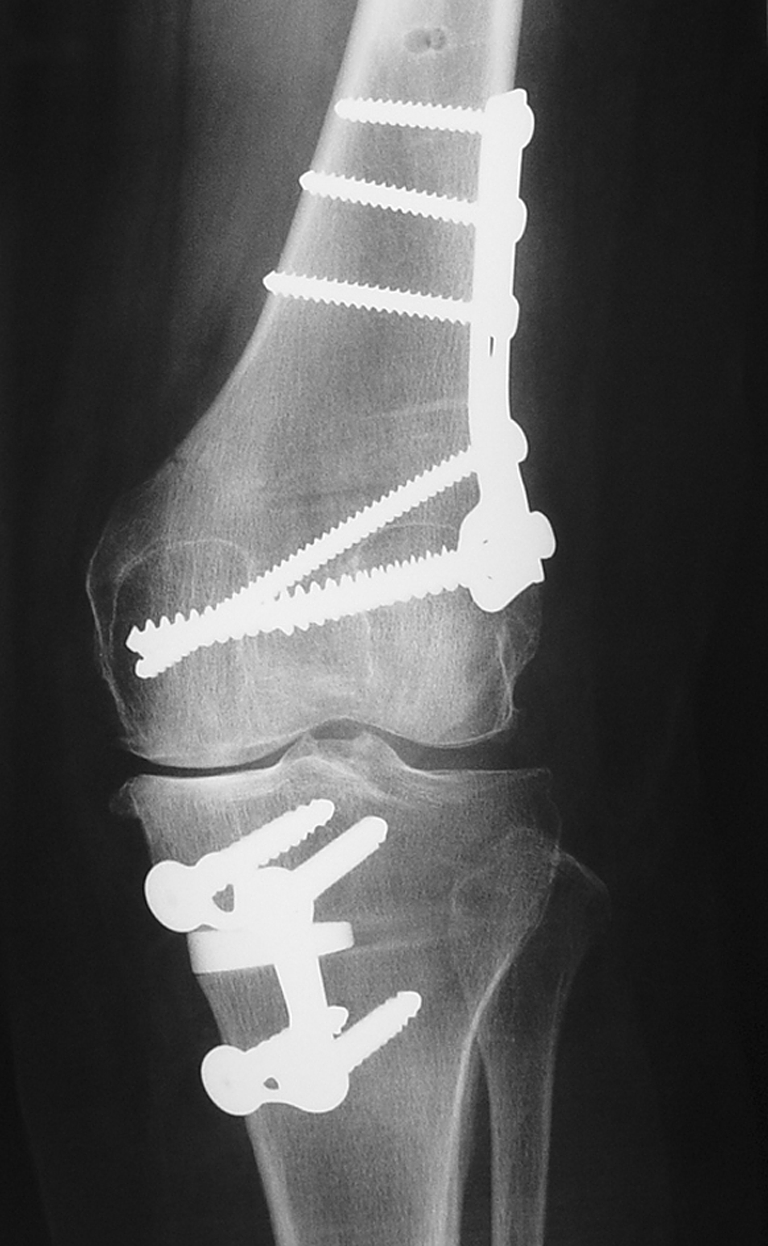

The last stage is to perform the HTO exactly in the fashion described above. The definitive axis is then displayed on the computer screen and the osteosynthesis is checked with an image intensifier (Fig. 6).

Fig. 6.

Radiological result of a double level osteotomy (DLO) (three-month follow-up)